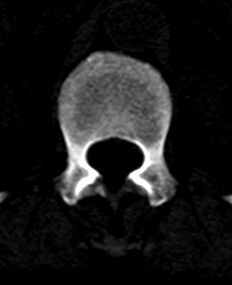

患者 女 54岁 外伤后检查发现l1椎体局部密度减低,请问这是什么病灶?

椎体内部局限性骨小梁稀疏、粗大改变,周围未见软组织肿块,首先考虑椎体血管瘤。